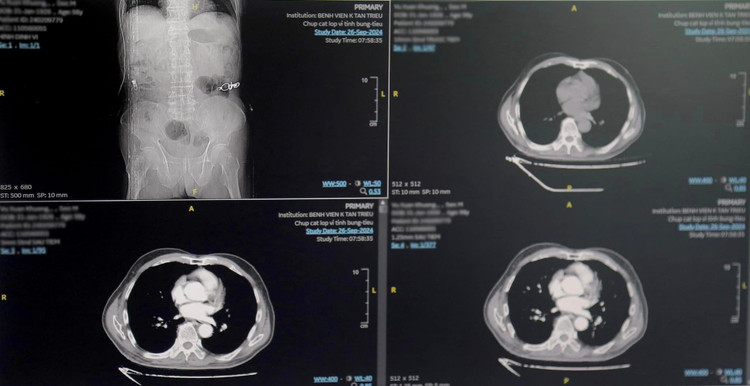

Từ các dấu hiệu bệnh của cụ Kh. và thông qua thăm khám lâm sàng, thực hiện các xét nghiệm, nội soi đại trực tràng, chụp CT, bác sĩ Bệnh viện K chẩn đoán bệnh nhân Kh.mắc ung thư đại tràng sigma, tổn thương u sùi thâm nhiễm gây chít hẹp, dày thành không đều quanh chu vi.

Tổn thương này đã gây mất cấu trúc các lớp ống tiêu hóa, thâm nhiễm rộng mỡ xung quanh và vùng hố chậu trái. Các vùng lân cận có vài hạch lớn, có hạch đường kính tới 26mm, bờ không đều. Người bệnh được chẩn đoán trước mổ: ung thư đại tràng Sigma T4bN2M0.

![]() |

| Khối u của bệnh nhân trên phim chụp - Ảnh BVCC |